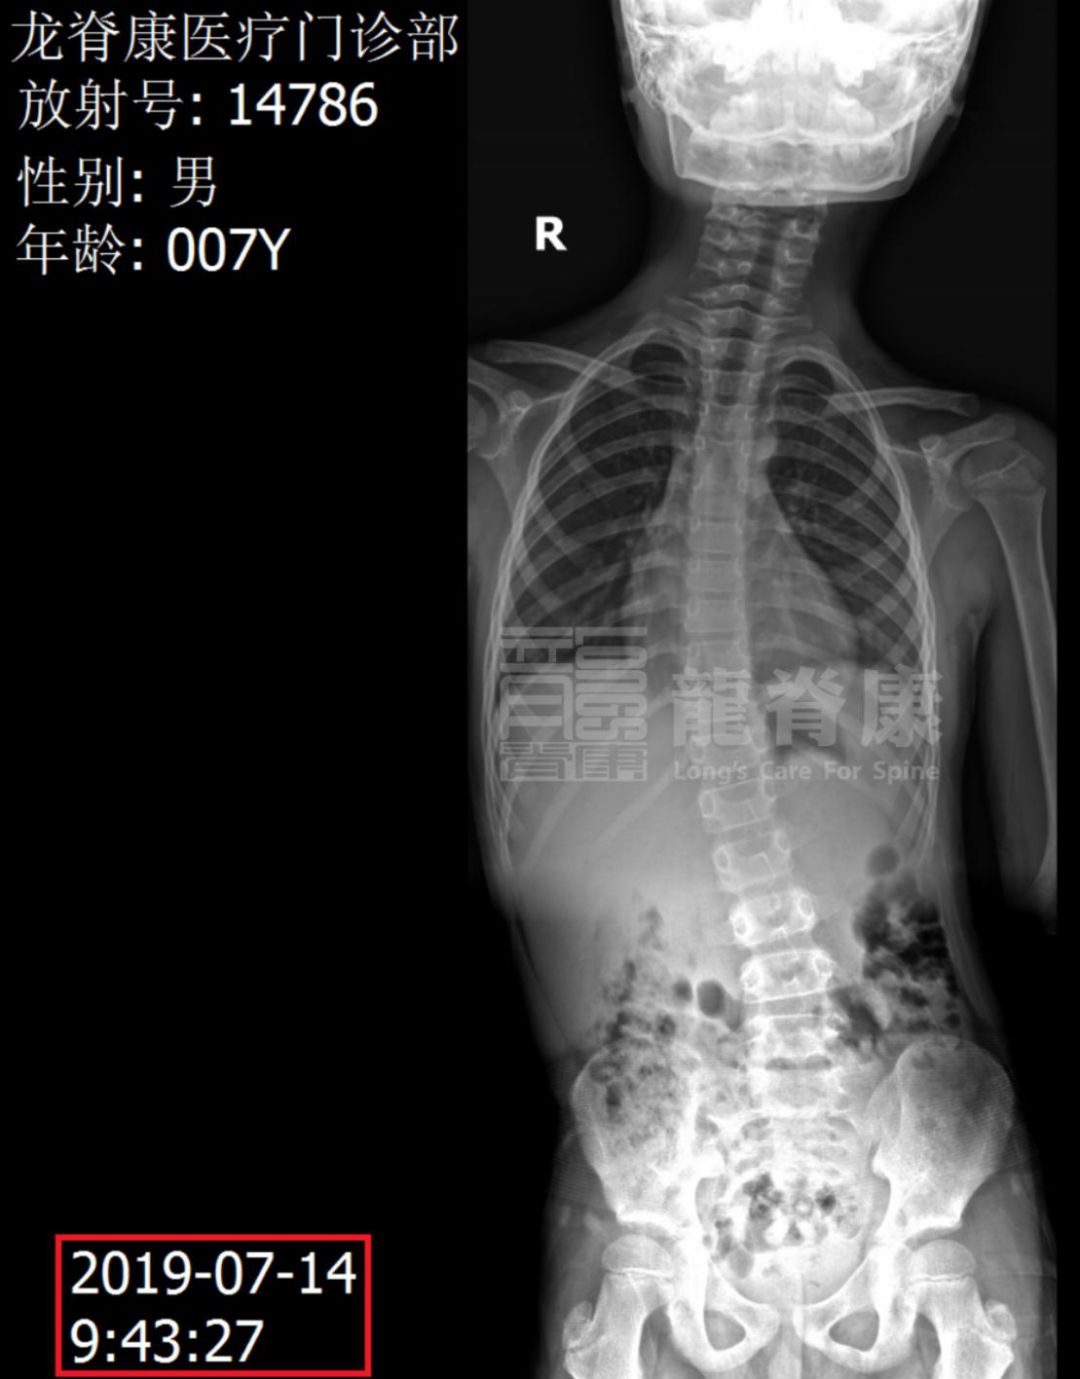

2019-7-14 9:43:27 片示脊柱侧弯28°▽

就诊时,查体发现孩子左肩高,左肩胛下角高,左侧背肌稍隆起,ATR(剃刀背)约3°。拍全脊柱x光片提示,脊柱往右侧凸,cobb角约28°,呈C型。可见:x光片与体查不符,结合椎体无明显旋转(脊柱侧弯多数伴随椎体旋转),剃刀背少于5°,可初步怀疑片子的真实性。